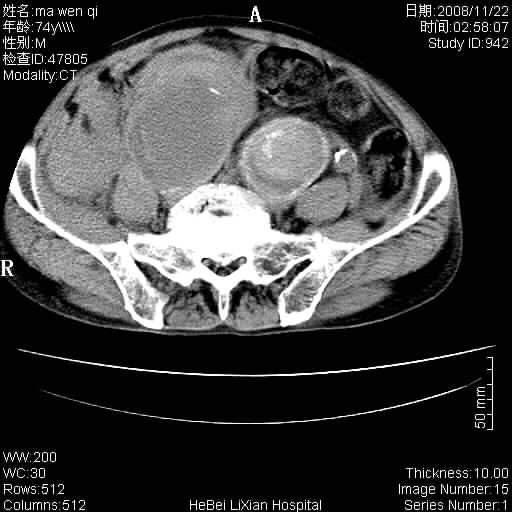

患者男 74岁.突然昏迷,休克6小时.血压70/30,头颅ct未见异常,既往体健.

补充病史,保留导尿10小时,尿袋内只有少许尿液,患者于住院后15小时后去世.

1)考虑双侧髂动脉瘤并右侧动脉瘤破裂出血,右侧腹膜后及腹腔积血。2)双侧腹股沟疝。

支持(1)双侧髂动脉瘤并右侧动脉瘤破裂出血,右侧腹膜后及腹腔积血。(2)双侧腹股沟疝。

1)考虑,腹主动脉、双侧髂动脉夹层动脉瘤破裂伴右侧腹膜后及腹腔积血。2)双侧腹股沟疝。

考虑双侧髂动脉瘤并右侧动脉瘤破裂出血,右侧腹膜后及腹腔积血;难见病例。谢谢